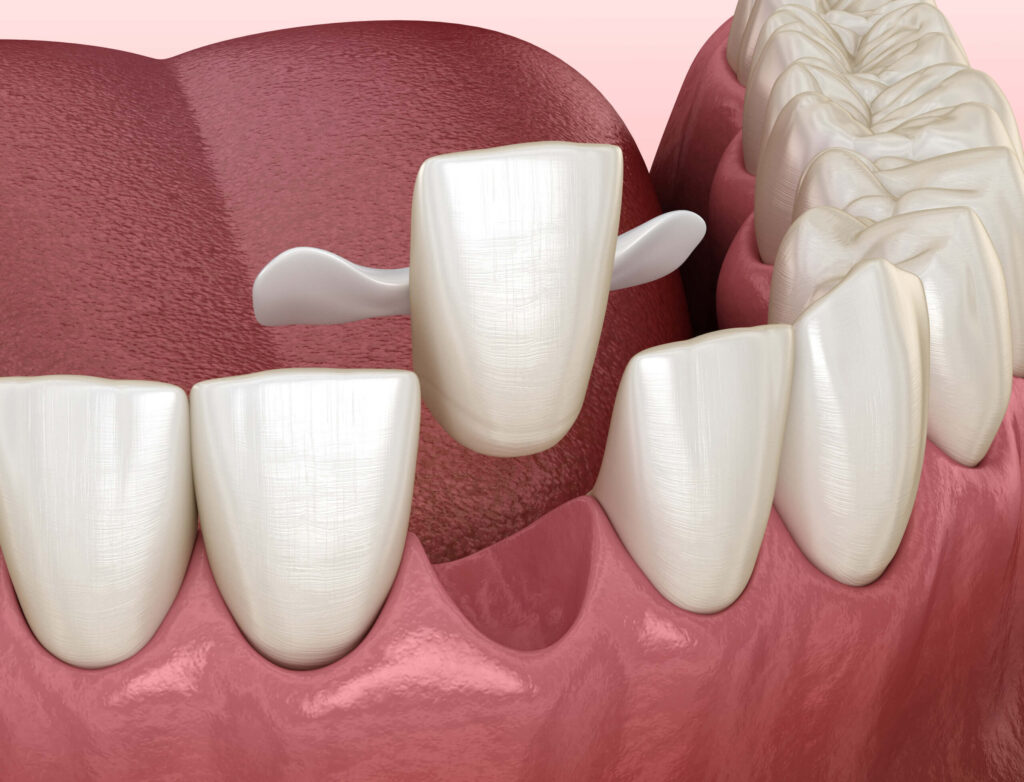

The Conservative Art of Smile Restoration: A Deep Dive into Maryland Bridges

In the bustling, fast-paced environment of Singapore, first impressions often matter significantly. Whether navigating the corporate hubs of Raffles Place or socializing in the vibrant neighborhoods of Tiong Bahru, a confident smile is a powerful social asset. However, tooth loss an issue affecting many due to decay, trauma, or periodontal disease can severely impact that […]